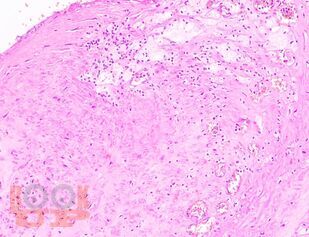

Учебное пособие разработано по дисциплине «Патологическая анатомия - патологическая анатомия головы и шеи» в соответствии с Федеральным государственным образовательным стандартом высшего профессионального образования для студентов, обучающихся по основным образовательным программам высшего образования - программам специалитета по специальности «Стоматология».

В учебном пособии представлен теоретический материал, перечень макропрепаратов и микропрепаратов, демонстрирующих типовые проявления патологических процессов. В цветных иллюстрациях и в описании микропрепаратов сделан акцент на наиболее важных гистологических изменениях, позволяющих на светооптическом уровне диагностировать и дифференцировать состояния, отклоняющиеся от нормы, в том числе с использованием различных гистологических окрасок. Пособие помогает выделить главные аспекты изучаемых патологических процессов, организовать и конкретизировать учебный процесс.